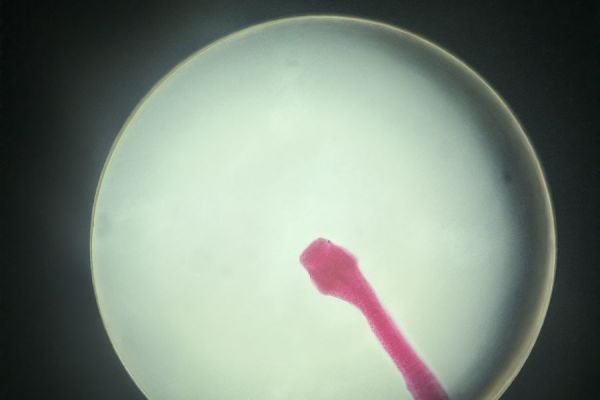

uczestniczyć w niezwykle ciekawych zajęciach w Zakładzie Biologii i Farmakognozji UMB. Podczas krótkiego, ale bardzo interesującego wykładu poznali cykle rozwojowe pasożytów, a następnie przenieśli teorię w praktykę, obserwując liczne preparaty mikroskopowe. Uczniowie oglądali m.in. lamblię, rzęsistka pochwowego, jaja tasiemca i glisty ludzkiej, wągry oraz główkę tasiemca uzbrojonego. Duże zainteresowanie wzbudziły również preparaty formalinowe tasiemca oraz wągra bąblowca.

Była to cenna lekcja biologii, która pozwoliła poszerzyć wiedzę, rozbudzić ciekawość naukową i zobaczyć „na własne oczy” to, o czym często mówi się tylko w podręcznikach.